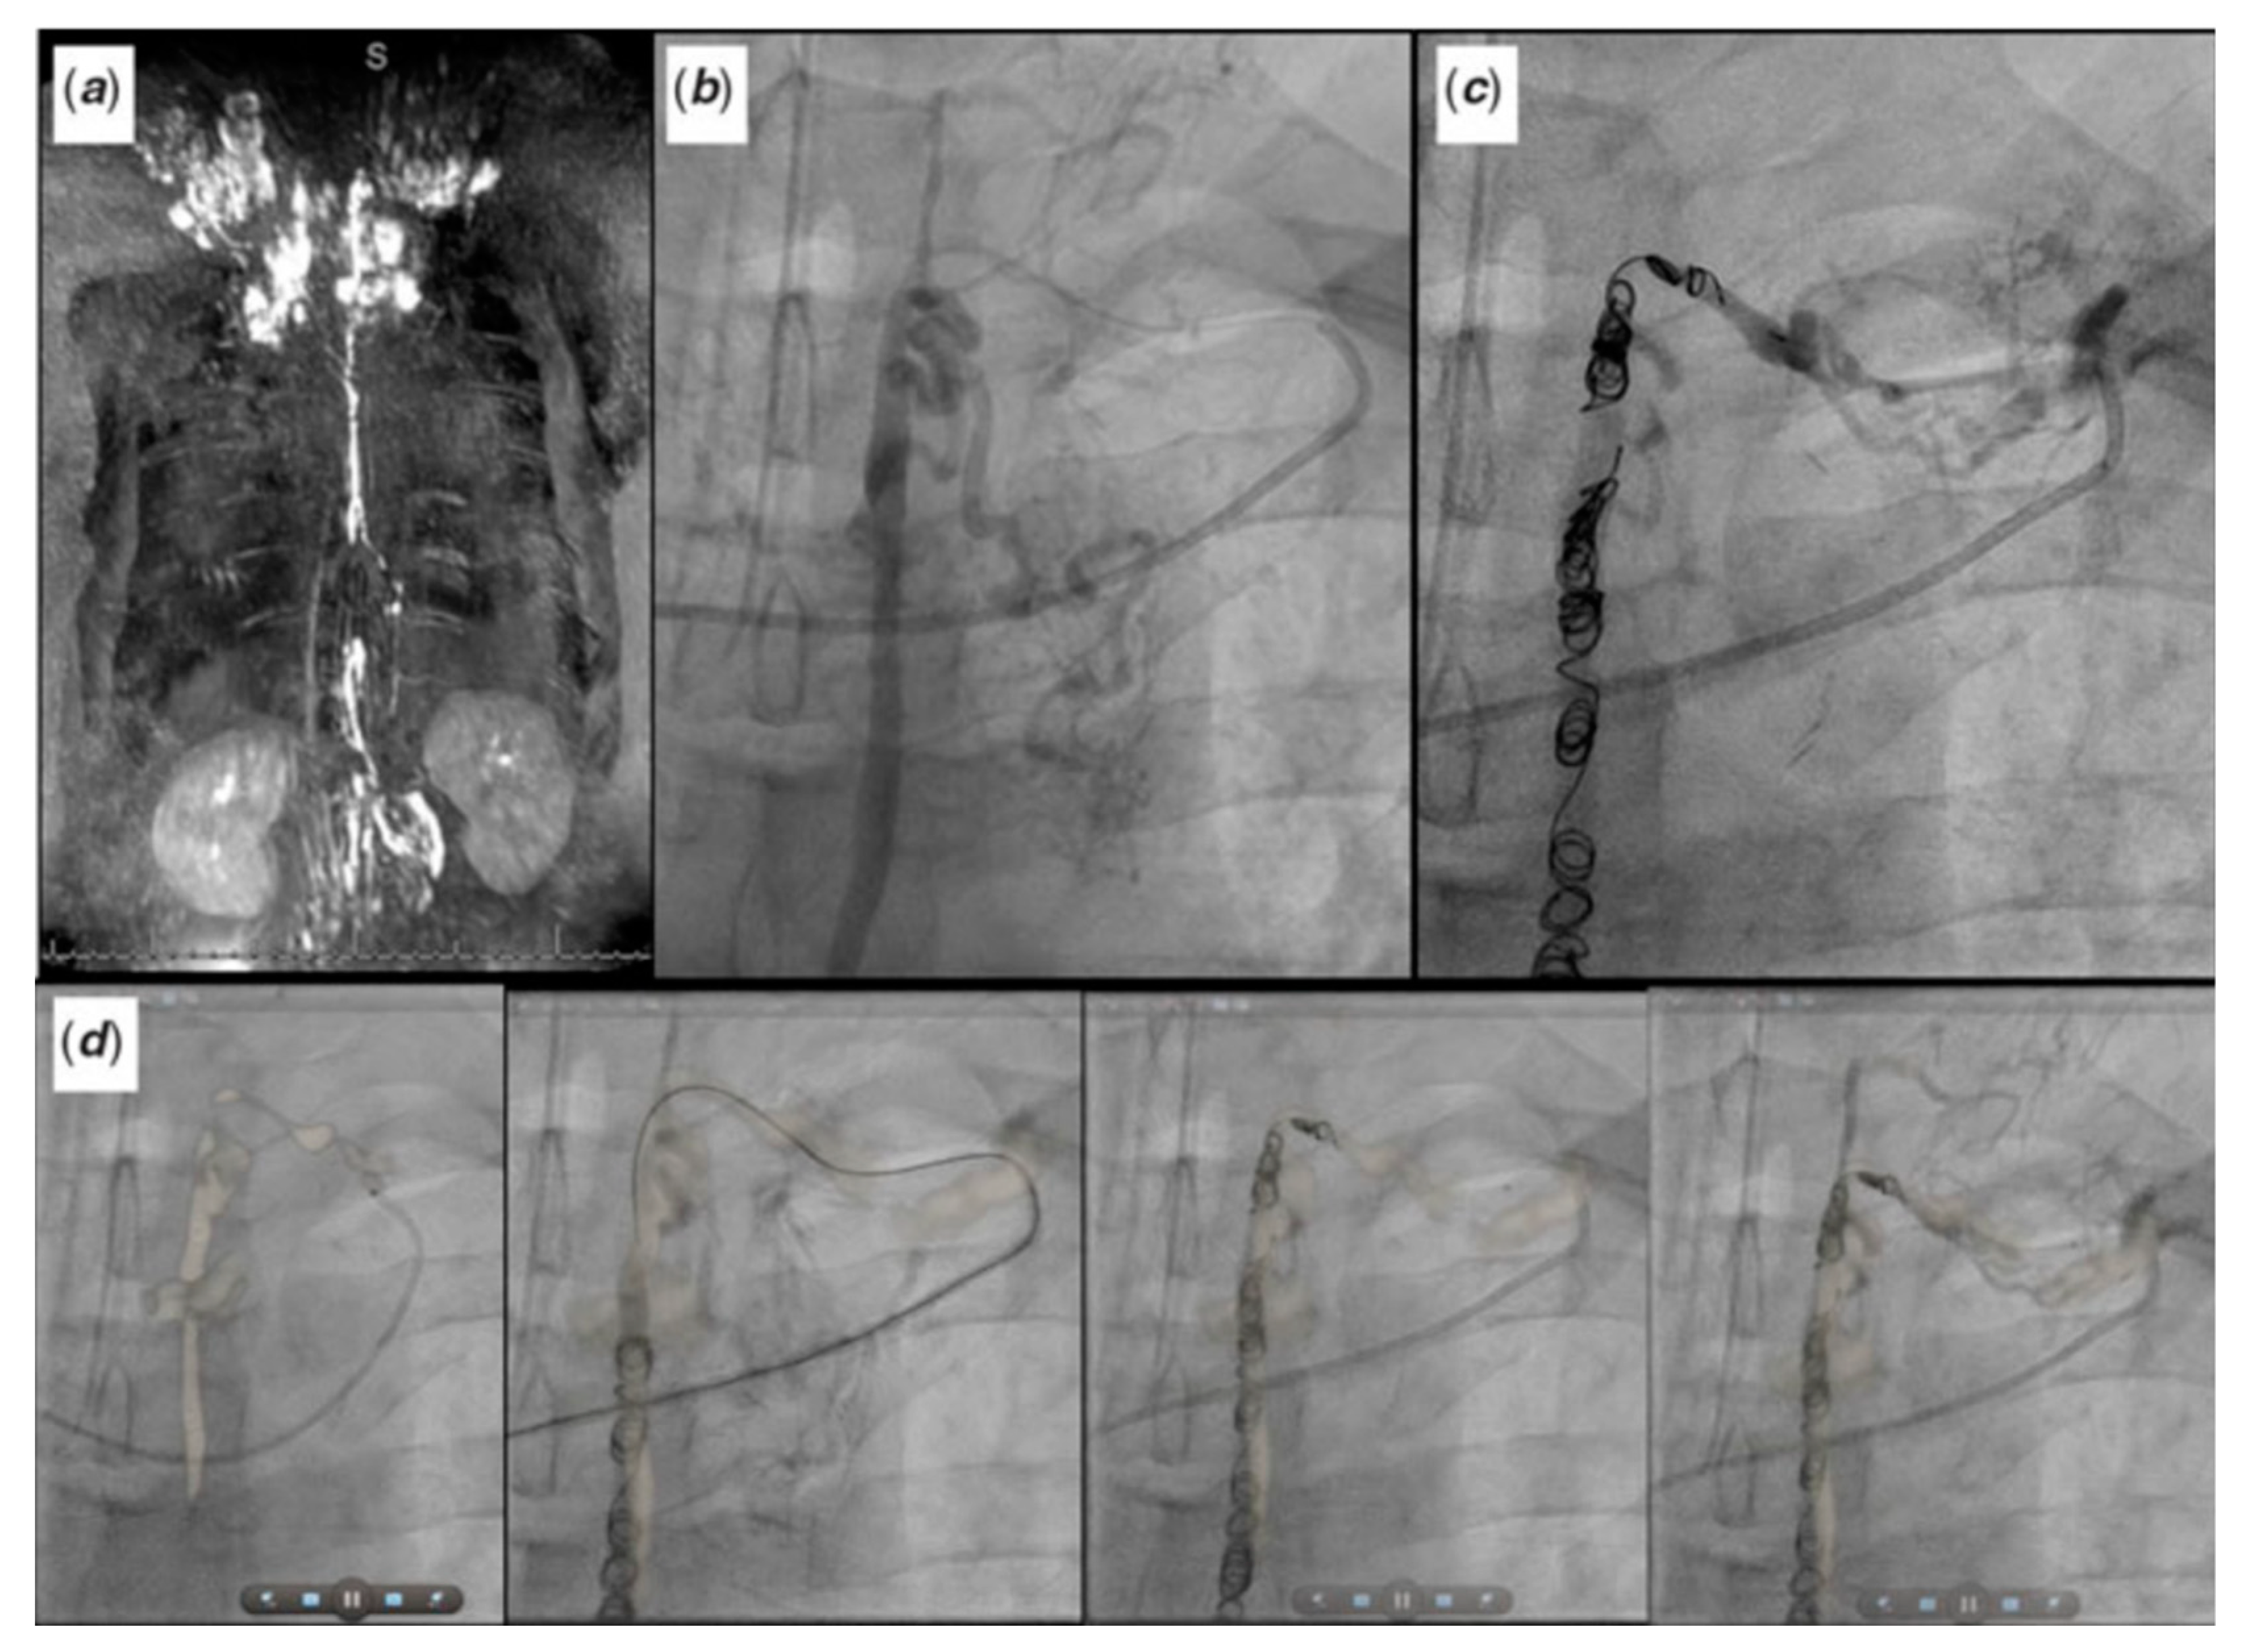

2.2. Patent Ductus Arteriosus (PDA) Stenting for Ductal-Dependent Pulmonary Blood Flow

2.2.1. Pre-Procedural

2.2.2. Post-Procedural